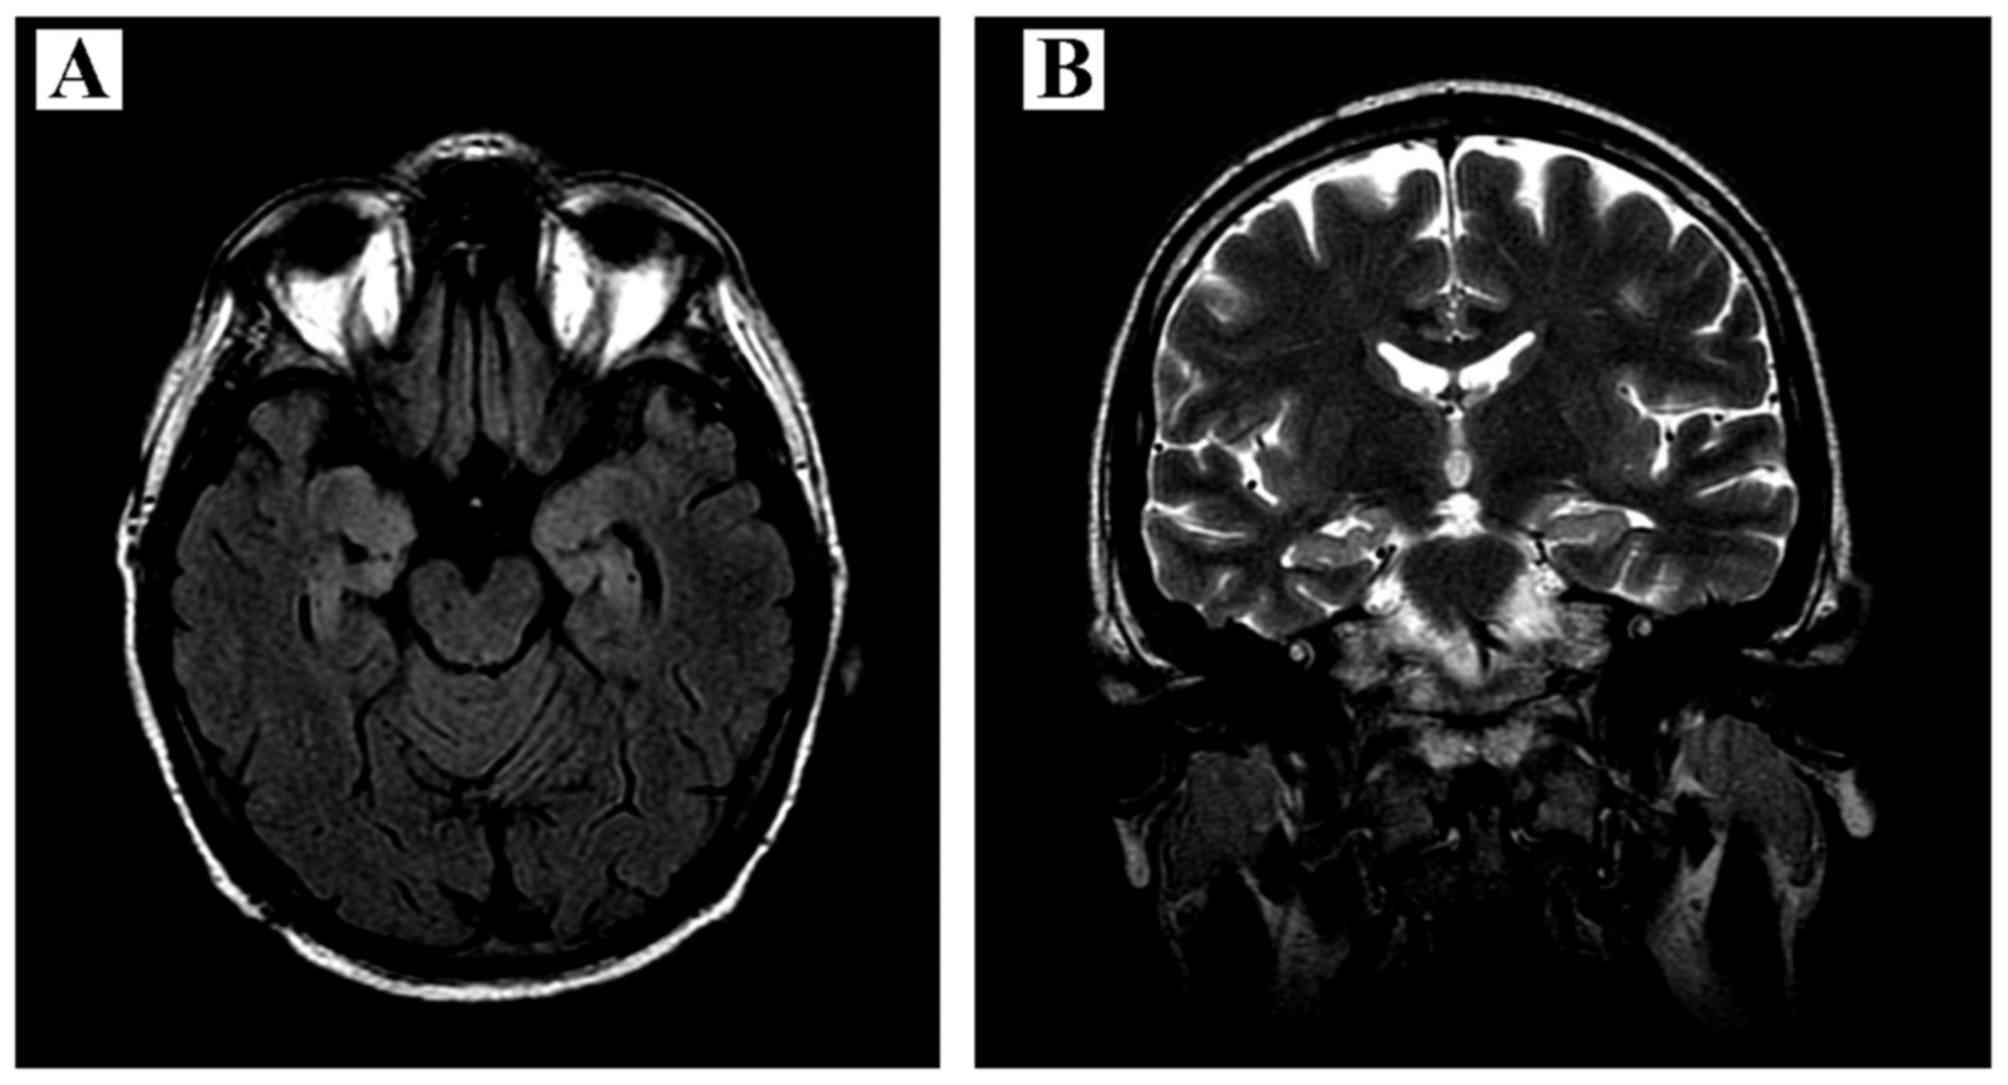

Paraneoplastic limbic encephalitis in a patient with extensive disease small‑cell lung cancer

Paraneoplastic limbic encephalitis (PLE) is a rare disorder infrequently accompanying malignancy, coexisting in ~50% of the cases with small‑cell lung cancer (SCLC). The pathomechanism of PLE is considered to be immune‑mediated, with production of specific anti‑Hu antibodies and activation of T‑cells directed against onconeural antigens present on both tumor cells and neurons. We herein report the case of a 50‑year‑old male patient who, prior to being diagnosed with SCLC, presented with typical symptoms of PLE (seizures, subacute cognitive dysfunction with severe memory impairment, anxiety and hallucinations). The initial brain magnetic resonance imaging examination revealed mild enlargement and hyperintensity of the hippocampal gyri bilaterally, with narrowed temporal horns of the lateral ventricles; the findings of the cerebrospinal fluid examination were compatible with the diagnosis of lymphocytic meningitis. Due to the suspected infectious origin of the disease, treatment with acyclovir and antibiotics was initially applied. However, following subsequent diagnosis of the underlying SCLC and the presence of antineuronal anti‑Hu antibodies in the patient's serum, the diagnosis of PLE accompanying extensive‑disease (ED) SCLC was confirmed. In addition to the standard cytotoxic therapy, throughout the course of his disease the patient also continued treatment with valproic acid (VPA) as prophylaxis for the initial seizures. VPA is known to be a potent histone deacetylase inhibitor that may reverse epigenetic changes in tumor cells and potentially improve the outcome of cancer patients. The patient succumbed to the disease 25 months after the diagnosis of malignancy; such a long course is observed in only ~5% of patients with ED SCLC. Therefore, it was hypothesized that the accompanying paraneoplasia and treatment with VPA may have improved the outcome in this patient.